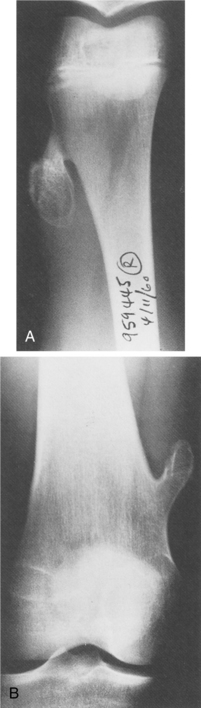

Those found in the long bones are usually in the diaphysis, although as with most tumors, they can be seen elsewhere (Fig. 26-5). The histologic makeup of osteoblastoma is very similar to that of an osteoid osteoma. In fact, sometimes it is size alone that differentiates the two, with osteoblastoma being the larger. The lesions are osteolytic and have a sclerotic border.

Figure 26-5 Genuine (conventional) osteoblastoma of the tibia in a 24-year-old woman. Anteroposterior (A) and lateral (B) radiographs show a round radiolucent lesion with slightly sclerotic borders at the lower and anterior aspect of the tibia. (From Gitelis S, Schajowicz F: Osteoid osteoma and osteoblastoma, Orthop Clin 20:320, 1989.)